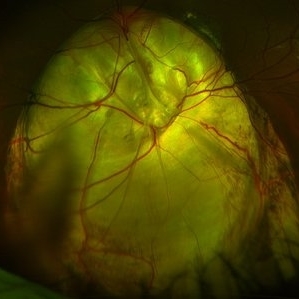

Fundus Coloboma

Fundus Coloboma

Feb 22 2023 by Zach Seim

An ultra-widefield fundus image of a 25 year old male with Fundus Coloboma, as well as Iris Coloboma affecting both eyes. Patient's vision at the time of the image was 20/100-2. Discussed genetic testing as patient reports that he has a child with coloboma and patient agrees. There is a possibility of this finding being syndromic given cornea has small WTW and possibly microphthalmia. The patient has old tractional exudation at edge (abutting fovea). Recommended observation without treatment.

Photographer: Zach Seim

Imaging device: Optos California

Condition/keywords: coloboma, coloboma of optic disc, fundus photograph, Optos, scanning laser ophthalmoscope, ultra-wide field imaging